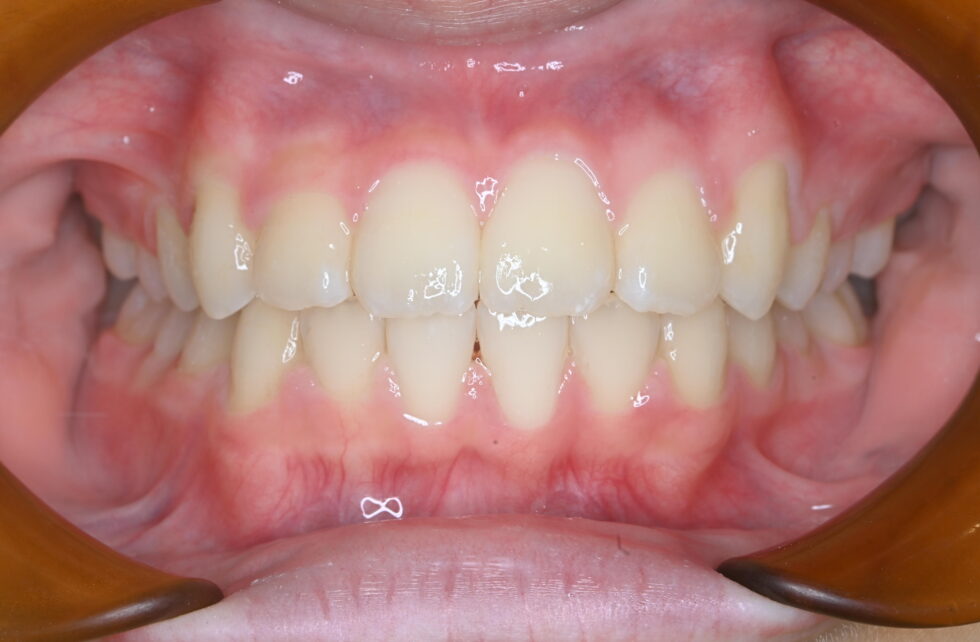

永久歯の配列余地が著しく不足していたが、上下顎の前後的なずれはなく中立咬合の叢生と診断した。Ⅰ期治療を7か月間(調整来院6回)行い、経過観察期間を経て13歳から上下顎マルチブラケット装置を使用して非抜歯でⅡ期治療を行った。Ⅱ期治療は来院間隔が長く2年6か月間を要したが、調整来院は14回であった。動的治療期間はⅠ期Ⅱ期合わせ3年1カ月間、調整来院は20回であった。

治療を受けようと思った理由は覚えてないけど、多分お母さんにすすめられたからだと思います。治療を受けてよかったことはやっぱり歯並びがきれいになって、治療を受ける前よりさらに全力で笑えるようになったことだと思います。治療を受ける前と後で変わったことは歯磨きです。しっかり歯磨きの指導まで行って下さるのでていねいに歯磨きするようになりました。ここのスタッフさんは本当に優しく1つ1つていねいなので、心配することはないと思います。またいつもきれいに保たれているので安心して通うことが出来ます。治療が終わった後のサプライズ(?)みたいなのも嬉しかったです。痛いことや我慢しなければいけないこともあるけど、絶対に綺麗な歯並びになるし、全力で笑えるようになるので安心して治療を受けて下さい♡